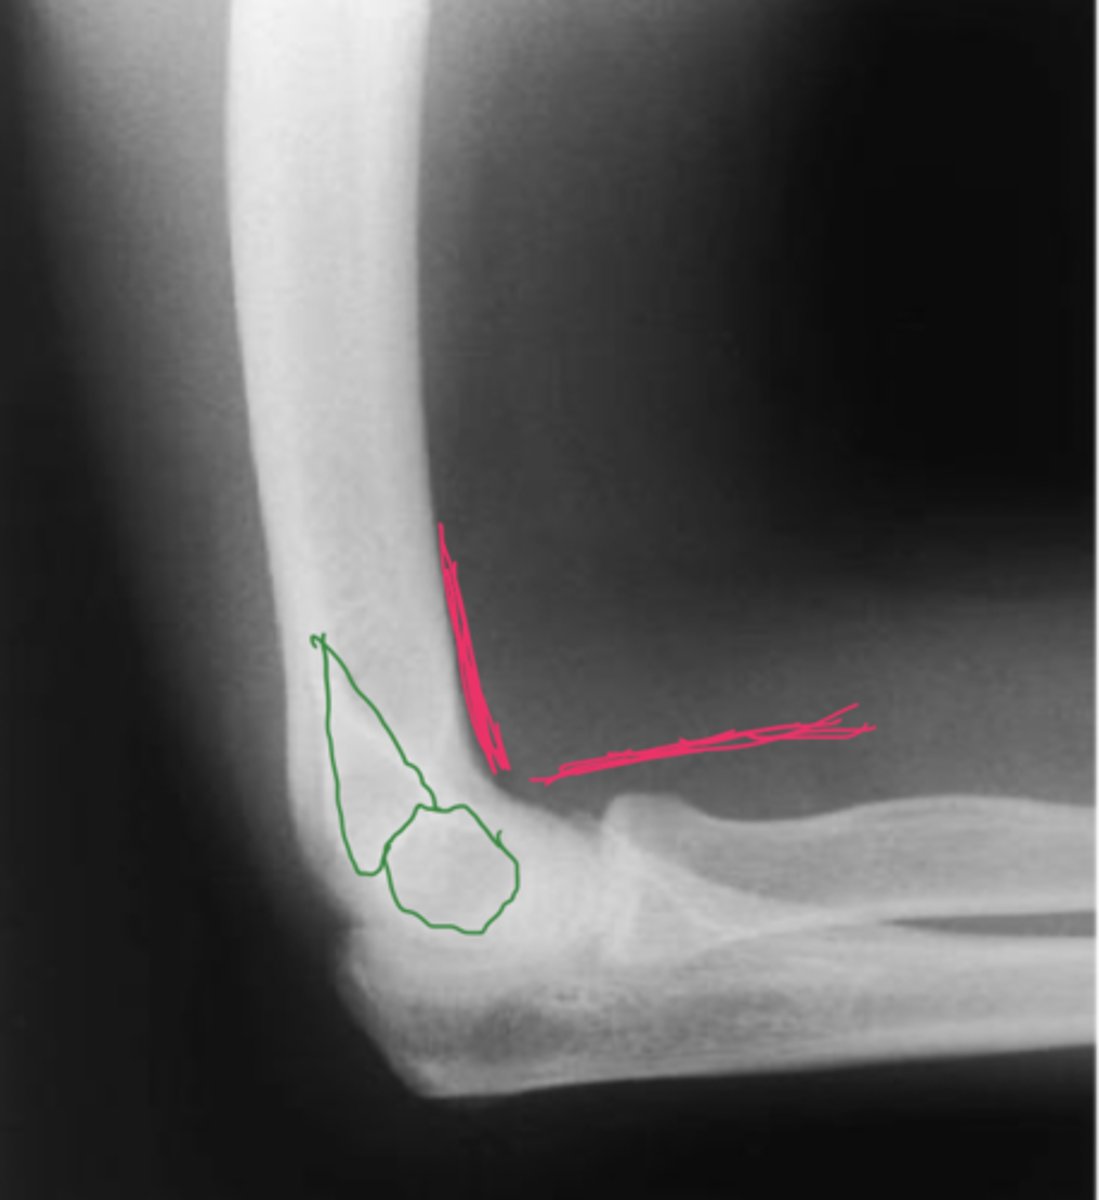

Myositis ossificans

What is the issue?

acute olecranon bursitis

positive fat pad sign